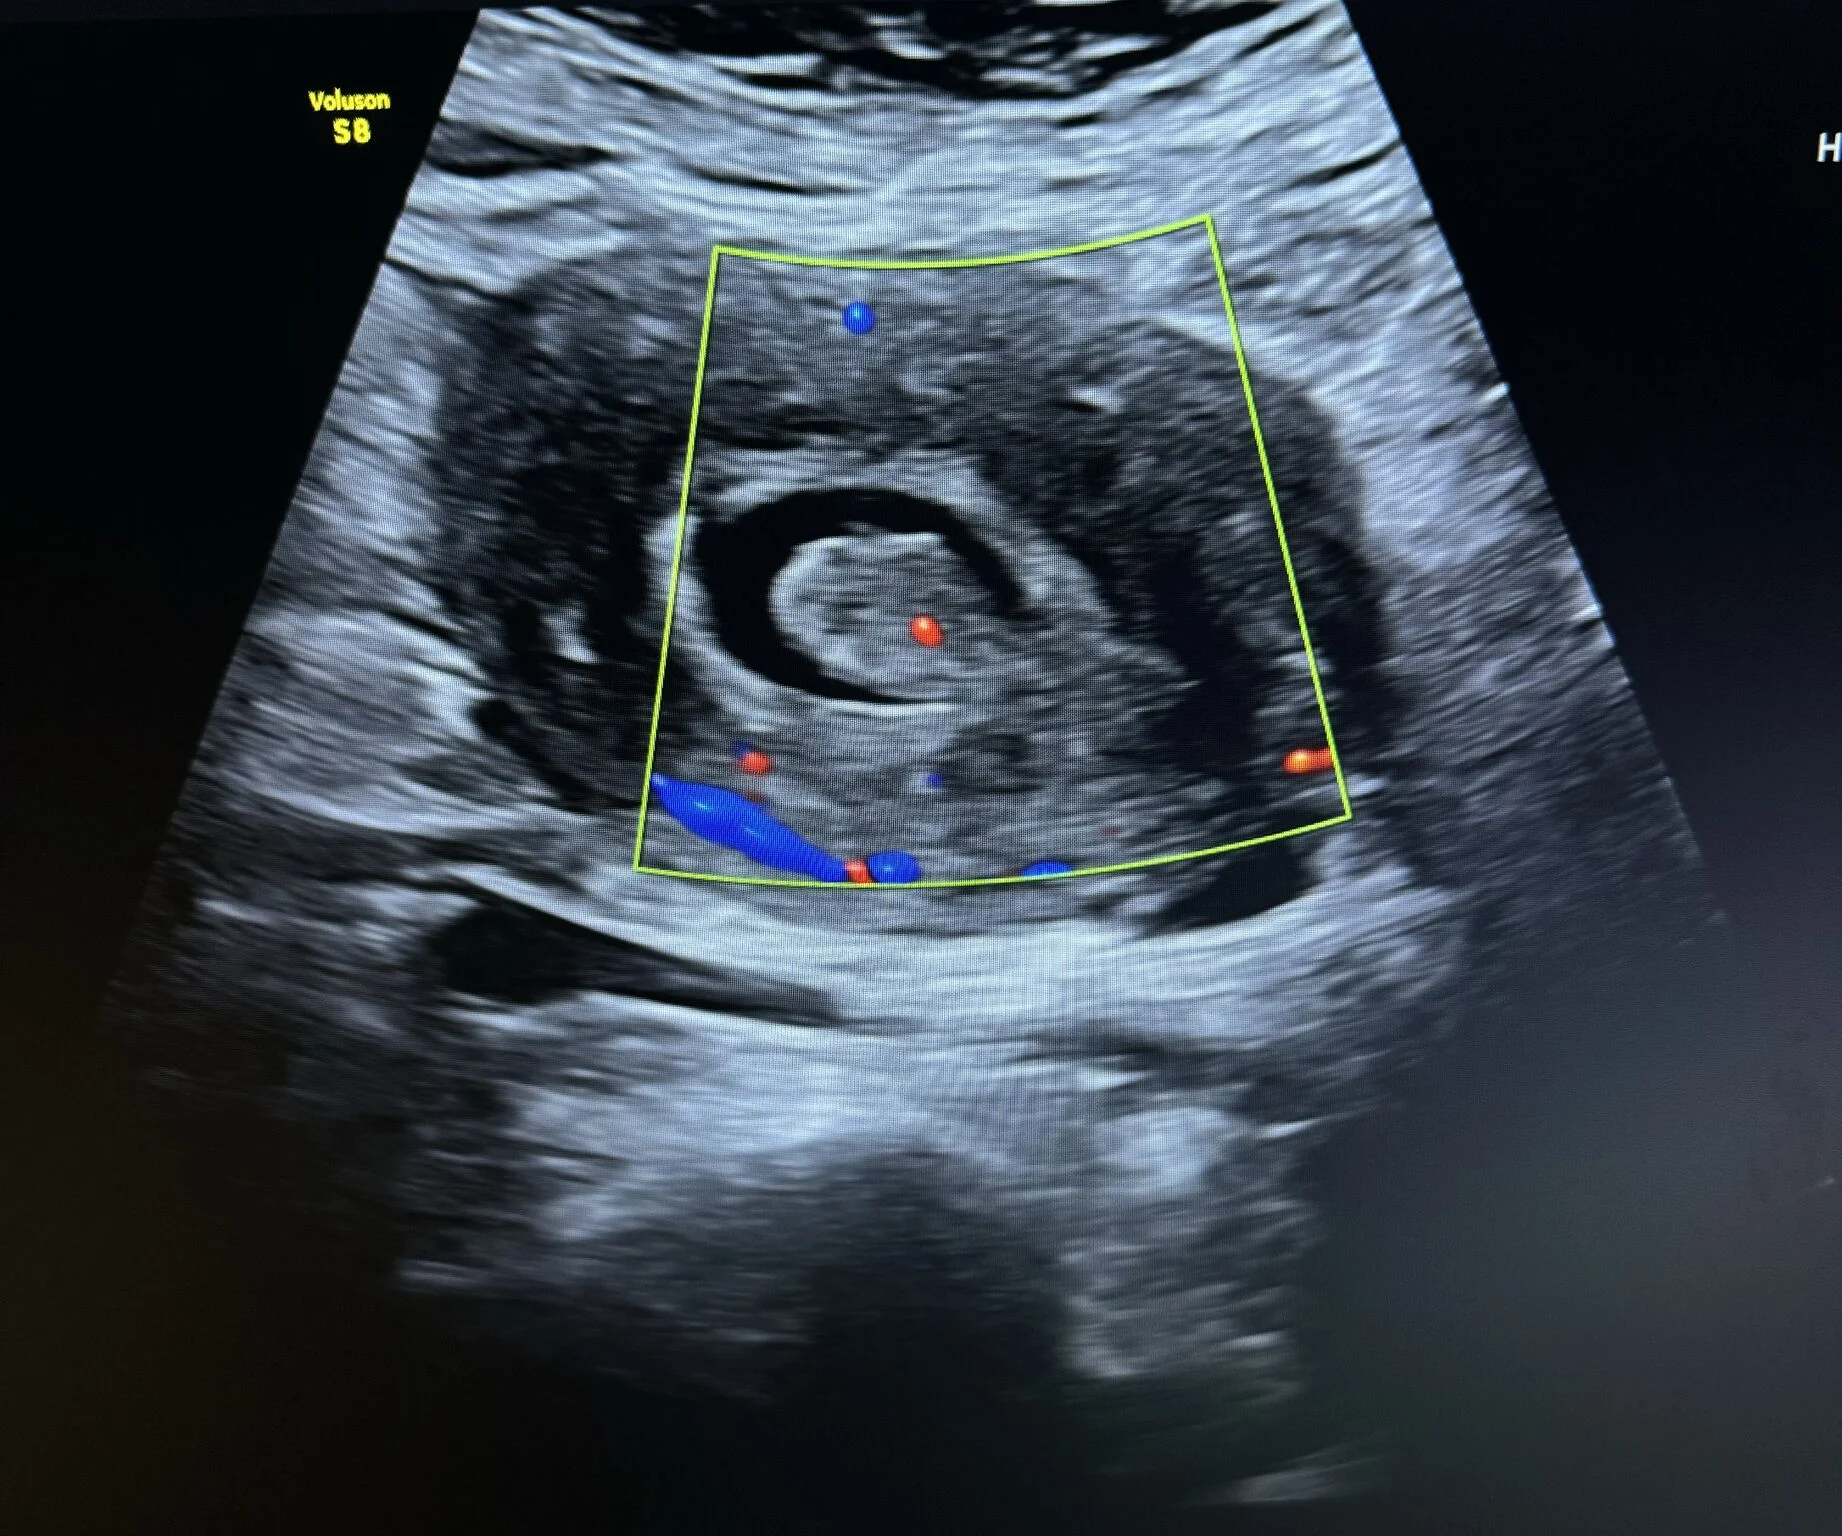

“Case Report: Uterine Polyp

A female patient presented to the clinic with complaints of abnormal uterine bleeding.

Ultrasound examination revealed a large endometrial polyp with notable vascular flow on color Doppler.

Ultrasound Appearance

On ultrasound, an endometrial polyp typically appears as a:

- Well-defined echogenic mass within the endometrial cavity

- Homogeneous texture

- Single central feeding vessel on color Doppler — a key feature distinguishing it from fibroids

Additional features:

- May appear as focal thickening or an oval-shaped lesion

- When using Saline Infusion Sonohysterography (SIS), the polyp can be clearly visualized moving freely within the fluid-filled cavity